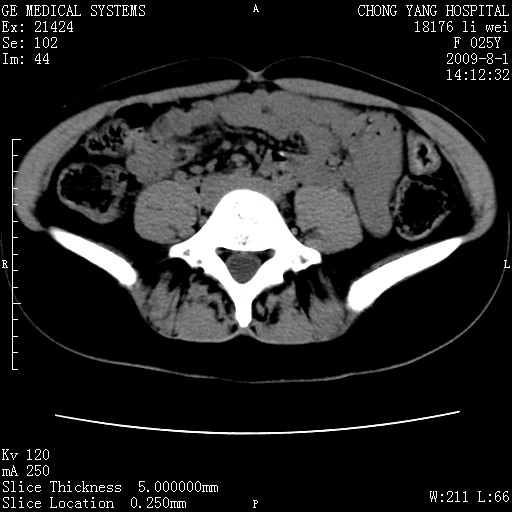

以下是引用pujunzhi在2009-8-1 20:23:00的发言:[br]胸椎旁及背部肌间良性病变,范围广,边界清,沿肌间生长,考虑淋巴管瘤、血管瘤,建议增强扫描。

以下是引用拾荒者在2009-12-30 21:45:00的发言:[br]ct21383:神经纤维瘤病( nf) [br] [br] 神经纤维瘤病。四肢都有,影响美观,四肢上的手术了。[br] [br] [br]谢谢!